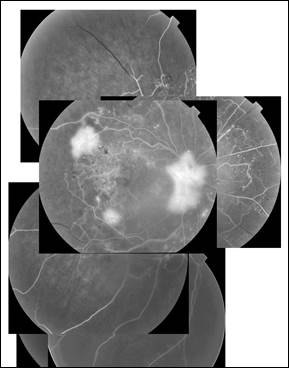

Цветное фотографирование и ФАГ выполнялись в 7 зонах (полях) сетчатки по Airlie House с помощью фундус-камеры TRC-NW7FF фирмы Topcon (Япония) с использованием цифровой системы IMAGEnet в условиях медикаментозного мидриаза до проведения ПРК (рис. 1) и через 3, 6, 12 месяцев после лазерного вмешательства. ФАГ проводилась в условиях медикаментозного мидриаза, достигаемого путем инстилляции 1% раствора мидриацила. Оценка флюоресцентных ангиограмм проводилась путем их визуальной расшифровки.

Рис. 1. Композиционный снимок данных флуоресцентной ангиографии левого глаза пациентки О. с тяжелой ПДР до проведения лазерного лечения.

Составлено авторами по результатам данного исследования